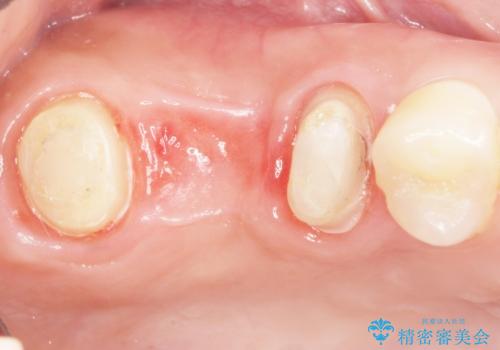

奥歯2本(右上76)はう蝕が深く保存不可能な状態であったため、やむなく抜歯しました。

使っていない親知らず(右上8)を右上7抜歯窩に移植し、支台歯としてブリッジによる補綴治療を行いました。